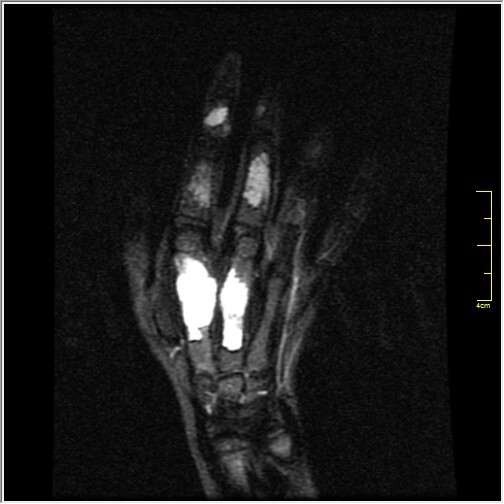

Welche Befunde erheben Sie auf dem vorliegenden Röntgen und MRT der Hand (T2fs und T1)? Verdachtsdiagnosen?